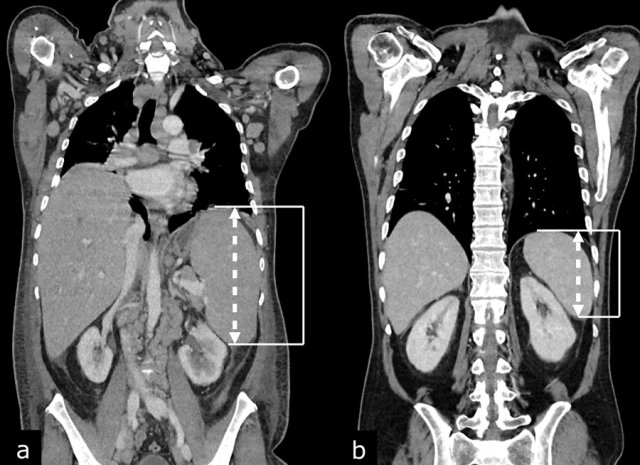

The CT images of a 82-year-old male show liver metastases of a GIST at baseline (arrowheads).

All metastases decrease somewhat in size after treatment with imatinib, but the most remarkable difference is a decrease in density.

This is considered to be a good response according to the Choi criteria.

The CT images in a 66-year-old male show liver metastases of a GIST at diagnosis (a).

At 3 months after treatment with imatinib there is a good response (b).

At a follow up scan at 1 year there is a  recurrence (arrow in c).

At a  follow-up after 2nd line treatment with sunitinib there is still tumor progression, but the size remains the same (d).